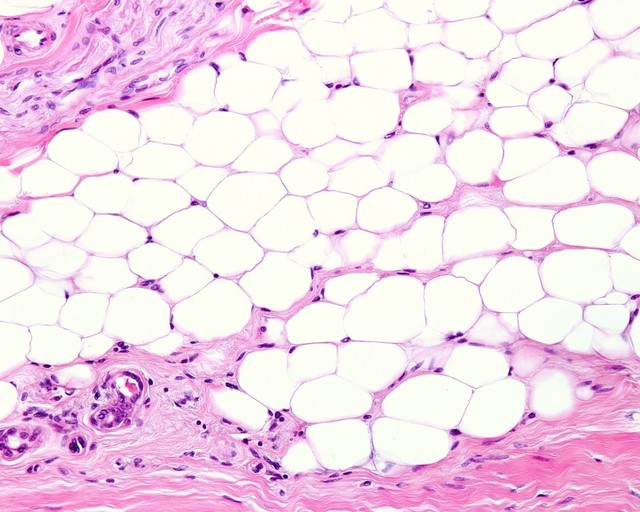

비가역적 지방세포 파괴 효과로 지방세포의 수가

감소되어 시간이 지나도 다시 예전처럼 돌아가지 않습니다.